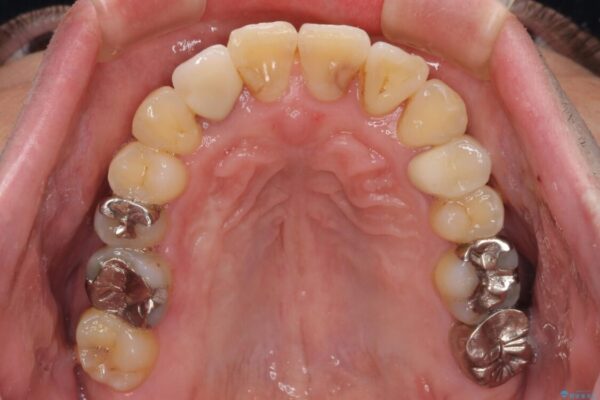

矯正治療でインプラント埋入を行い、矯正治療後に気になる前歯と合わせてオールセラミッククラウンによる補綴治療を行うこととしました。

骨造成や歯肉移植など、治癒期間の長い処置を必要としたため治療期間は長くなりましたが、安定した咬み合わせと整った歯列となり、患者様には大変満足していただきました。

治療後

• 割れてしまった奥歯とデコボコの前歯 矯正治療とインプラント治療 治療後画像